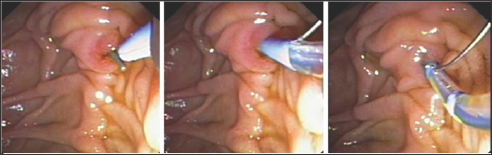

Figure 1: A Guidewire passing through the ampulla was captured by a snare and then withdrawn through the endoscopic working channel.

During ERCP cannulation was performed using standard method and accessories. The distal CBD was of a diameter of 0.8 cm and a tight stricture almost at the anastomosis where the guidewire could not be passed more proximally through the very tight stricture by any means [7]. So, the decision was to proceed with Rendezvous procedure with the aid of interventional radiologist. The percutaneous puncture was performed aided by ultrasound and access was gained into the mildly dilated right hepatic bile duct. The guidewire was introduced through the right intrahepatic duct through the anastomosis, where after few trials the wire had been passed through the stricture into CBD then out of the ampulla of vater. Then, using the duodenoscope the wire coming out the ampulla of vater was pulled into the scope channel and a sphincterotome was passed over the guidewire into CBD then across the stricture successfully. Finally a plastic stent of 7 F*7 cm was inserted successfully through the stricture with good bile drain. The percutaneous rendezvous procedure enabled placement of an internal-external drain [8]. One week after the procedure the patient reported having right sided chest pain along with progressive shortness of breath. The chest Xray showed a massive right sided pleural effusion. Paracenthesis revealed an exudative bilious fluid. The external drain was removed followed by replacement of a longer new internal plastic stent placement. The right pleural fluid reacumulation was diminished significantly and the patients shortness of breath improved dramatically (Figures 1-4).